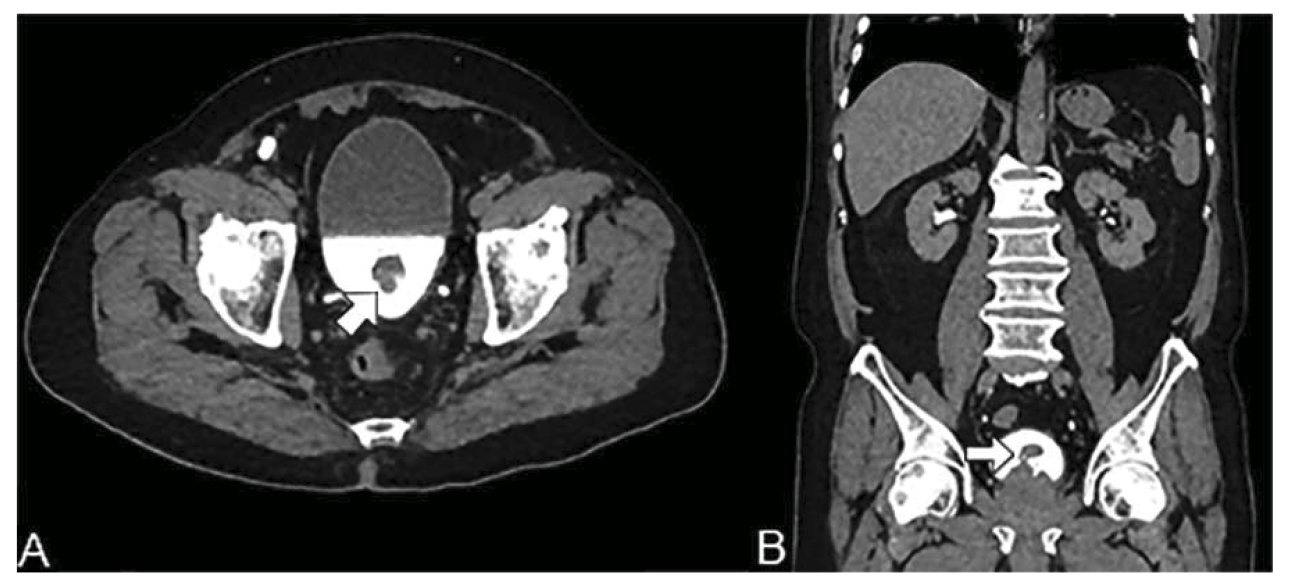

A nivel de vejiga, se observó engrosamiento de la pared posterior con realce hasta las 76 Unidades Hounsfield (UH) en la fase arterial, y un defecto de llenado de 12 mm en la fase de eliminación (figura 2).